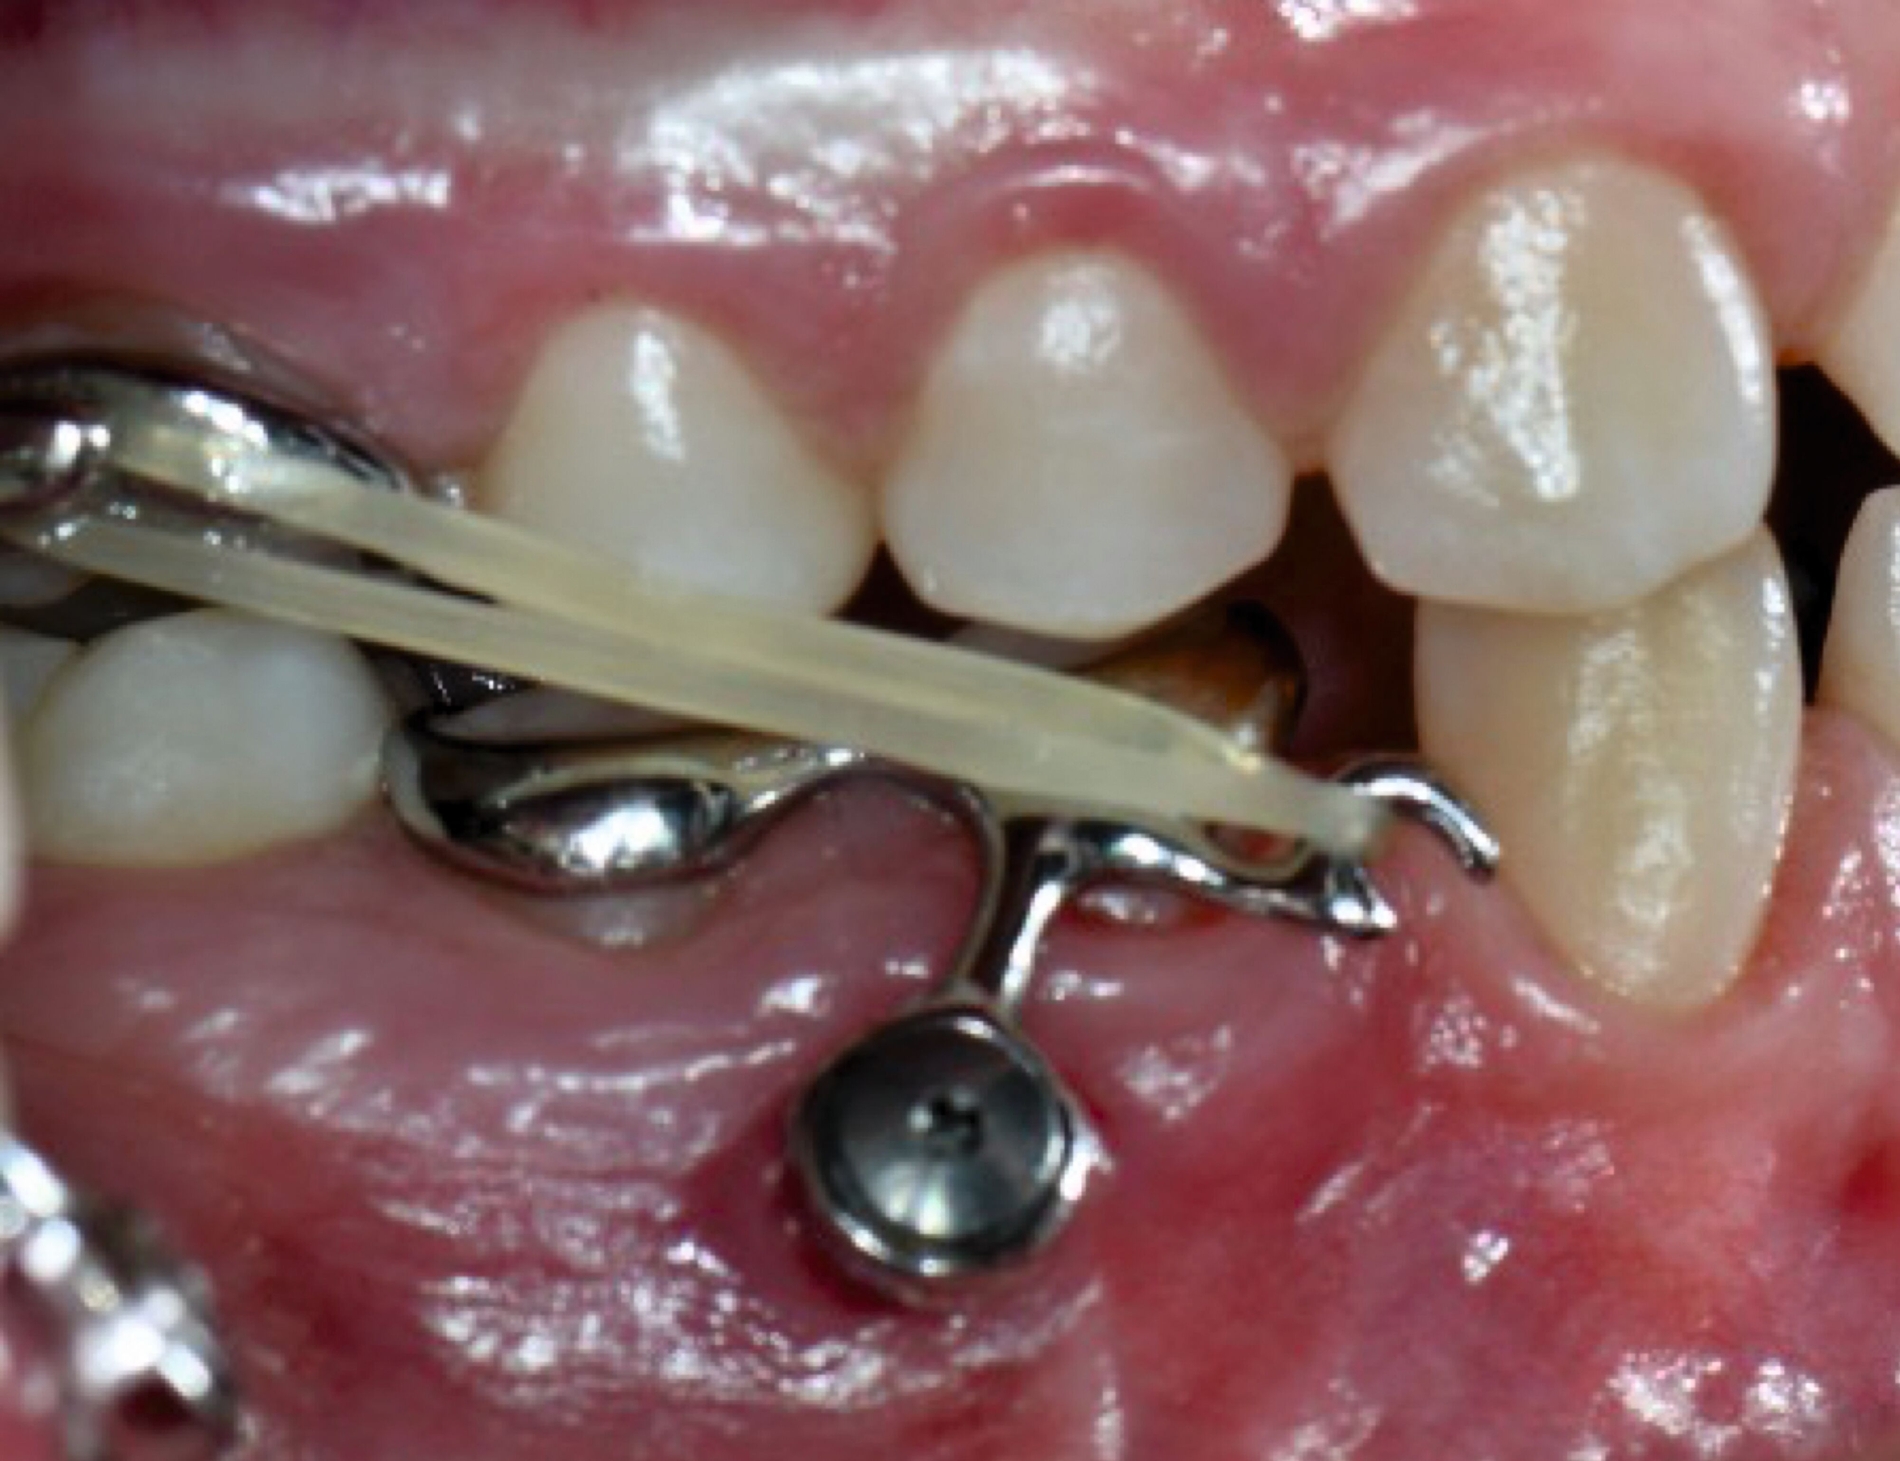

Die Gruppe der 3-D-gedruckten Metallapparaturen dürfte bisher am meisten vom 3-D-Druck profitiert haben. Regelhaft werden hierfür noch Cobalt-Chrom-basierte Materialien im Stereolithografie-Verfahren (SLM) verwendet. Aufgrund einer höheren Biokompatibilität nimmt der 3-D-Druck von Titan-basierten Materialien jedoch zu.

Anwendung findet der Metalldruck vor allem in der Herstellung skelettal verankerter Apparaturen, durch die reziproke Kräfte auf orthodontische Miniimplantate abgeleitet oder direkt skelettal aufgebracht werden können. Neben einer hohen Passgenauigkeit liegt der Vorteil vor allem in einer zielgerichteteren Therapie, die die anschließende oder zeitgleich durchgeführte Aligner- beziehungsweise Multibracket-Therapie verkürzt. Weiter können orthodontische Behandlungsaufgaben gelöst werden, die unter alleiniger Nutzung von Alignern beziehungsweise einer Multibracket-Apparatur deutlich limitiert wären. Beispiele beinhalten sogenannte „Mesialslider“ [Wilhelmy et al., 2022], „Distalslider“ [Graf et al., 2020] oder „Intrusionsapparaturen“.

Weiter erlauben hochindividuelle 3-D-gedruckte Designs die Therapie von skelettalen Fehlständen, beispielsweise in der Therapie defizitärer Maxillae [Pasqua et al., 2022; Bazargani et al., 2023; Ludwig et al., 2024] oder im Rahmen der nonoperativen oder postoperativen Prognathie-Behandlung [Hodecker et al., 2023]. Auch die Umsetzung skelettal verankerter Apparaturen mittels nichtmetallischer 3-D-Druckmaterialien findet in einzelnen Fällen Anwendung (Abbildung 3b). Zum Einbringen der Miniimplantate eignen sich sogenannte 3-D-gedruckte „Insertions-Guides“, die nach vorheriger digitaler Planung der Miniimplantat-Position, eine hochgenaue Insertion ermöglichen [Wilmes et al., 2022; Wilmes et al., 2022]. Die virtuelle Planung der Minischraubeninsertion ermöglicht eine sichere und nachvollziehbare Evaluation sämtlicher relevanter Gewebe, um die ohnehin geringen Risiken weiter zu minimieren. Zusätzlich kann man die Biomechanik der digital geplanten kieferorthopädischen Apparatur ideal koordinieren und – wenn man möchte – die Minischrauben und die Apparatur in einer Sitzung einsetzen.